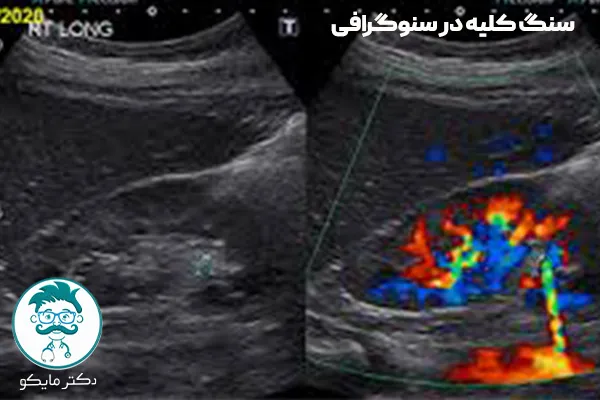

سنگ کلیه جزو بیماریهای دستگاه ادراری به حساب میآید که در طول سال افراد زیادی به آن مبتلا میشوند. در یک اصطلاح کوتاه، سنگ کلیه عبارت است از انباشته و جمع شدن املاح معدنی در قسمت مجاری کلیوی. به عبارتی دیگر، سنگ موجود در کلیه ها جسم سختی است که بر اثر پیوستن مواد موجود در ادارار تشکیل میشود.

علائم سنگ کلیه در آزمایش ادرار